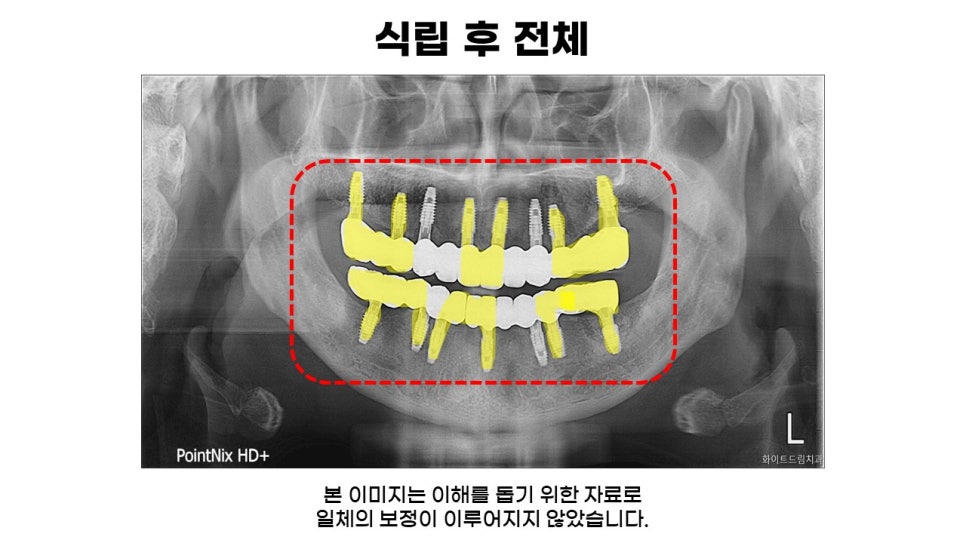

보여드리는 사진은 전체임플란트식립 후의 모습입니다.

상악과 하악 임플란트 모두 각도와 간격이 적절하게 식립됐으며, 신경을 건드리지 않도록 면밀하게 진행해드렸는데요.

추가적인 통증 없이 자연치와 유사하게 기능성과 심미성 회복을 도와드렸습니다.